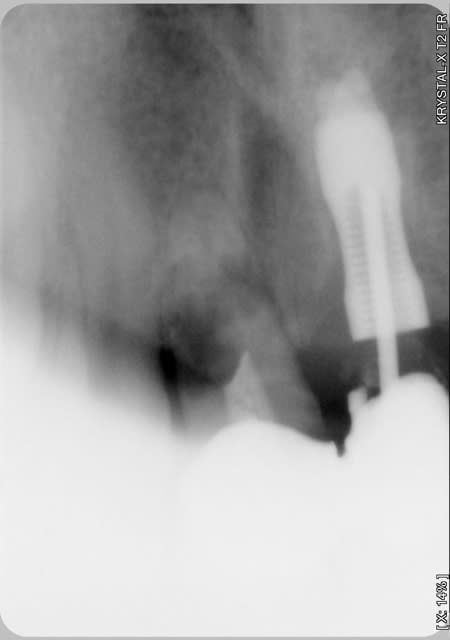

J'ai besoin d'un coup de main pour reconnaitre un implant qui a été posé sur un de mes patients (originaire de république tchèque).

Donc si quelqu'un reconnait le type d'implant et la marque à l'aide de la radio je l'en remercie.